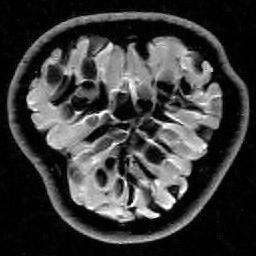

|

|

|

| Original image | Gauss. to DB4, err=31.54% | Gauss. to Flip DB4, err=31.51% |

|

|

|

| Subsampling pattern | DFT to DB4, err=10.96% | DFT to Flipped DB4, err=99.3% |

Since it will become important later, we now describe a quick and simple test, which we call the flip test, to investigate the presence or absence of an RIP. Success of this test suggests the existence of an RIP and failure demonstrates its lack.

Let be a sensing matrix, an image and a sparsifying transformation. Recall that sparsity of the vector is unaffected by permutations. Thus, let us define the flipped vector

and using this, we construct the flipped image Note that, by construction, we have . Now suppose we perform the usual compressed sensing reconstruction (1) on both and , giving approximations and . We now wish to reverse the flipping operation. Thus, we compute which gives a second approximation to the original image .

This test provides a simple way to investigate whether or not the RIP holds. To see why, suppose that satisfies the RIP. Then by construction, we have that

Hence both and should recover equally well. In the top row of Figure 1 we present the result of the flip test for a Gaussian random matrix. As is evident, the reconstructions and are comparable, thus indicating the RIP.

Having considered type II problems, let us now examine the flip test for a type I problem. As discussed, in applications such as MRI, X-ray CT, radio interferometry, etc, the matrix is imposed by the physical sensing device and arises from subsampling the rows of the DFT matrix .111In actual fact, the sensing device takes measurements of the continuous Fourier transform of a function . As discussed in BAACHGSCS ; BAGSAIEP , modelling continuous Fourier measurements as discrete Fourier measurements can lead to inferior reconstructions, and worse, inverse crimes. To avoid this, one must consider an infinite-dimensional compressed sensing approach, as in (2). See AHPRBreaking ; BAGSAIEP for details, as well as PruessmannUnserMRIFast for implementation in MRI. However, for simplicity, we shall continue to work with the finite-dimensional model in the remainder of this paper. Whilst one often has some freedom to choose which rows to sample (corresponding to selecting particular frequencies at which to take measurements), one cannot change the matrix .

It is well known that in order to ensure a good reconstruction, one cannot subsample the DFT uniformly at random (recall that the sparsifying transform is a wavelet basis), but rather one must sample randomly according to an appropriate nonuniform density AHPRBreaking ; Candes_Romberg ; Lustig ; WangAcre . See the bottom left panel of Figure 1 for an example of a typical density. As can be seen in the next panel, by doing so one achieves a great recovery. However, the result of the flip test in the bottom right panel clearly demonstrates that the matrix does not satisfy an RIP. In particular, the ordering of the wavelet coefficients plays a crucial role in the reconstruction quality. To explain this, and in particular, the high-quality reconstruction seen in the unflipped case, one evidently requires a new analytical framework.

Note that the flip test in Figure 1 also highlights another important phenomenon: namely, the effectiveness of the subsampling strategy depends on the sparsity structure of the image. In particular, two images with the same total sparsity (the original and the flipped ) result in wildly different errors when the same sampling pattern is used. Thus we conclude that there is no one optimal sampling strategy for all sparse vectors of wavelet coefficients.